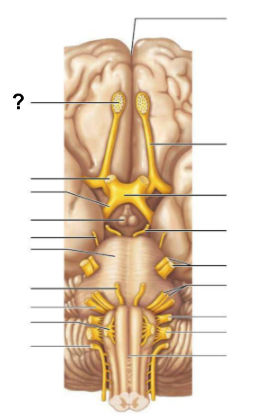

What structure, labeled “?”, is the starting point of cerebrospinal fluid circulation in the brain?

Lateral ventricle

From the lateral ventricles, CSF flows through which structure, labeled “?”, to reach the third ventricle?

Interventricular foramen

After the third ventricle, CSF flows through which narrow passage, labeled “?”, to reach the fourth ventricle?

Cerebral aqueduct

What are the two apertures, labeled “?”, through which CSF exits the fourth ventricle to enter the subarachnoid space?

The median aperture and the lateral apertures

Which structure surrounds the brain and spinal cord, allowing CSF to circulate?

Subarachnoid space

Through which structure, labeled “?”, is CSF absorbed into the venous blood?

Arachnoid villi

Into which venous system does CSF drain after passing through the arachnoid villi?

Dural venous sinuses

What is the function of the central canal in CSF circulation?

The __________ is responsible for processing olfactory (smell) signals before sending them deeper into the brain

Olfactory bulb

The __________ carries olfactory information from the olfactory bulb to the brain

Olfactory tract